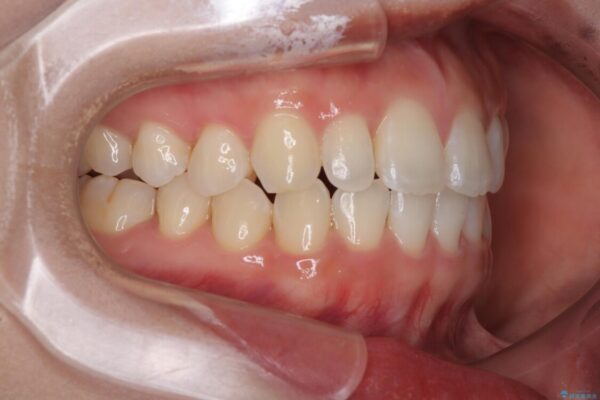

前歯のデコボコが気になるでのことで来院された患者様です。

歯列アーチが狭くスペース不足により前歯がデコボコしている状態でした。見た目を改善しつつ、前歯を前方に突出させず、自然な笑顔を目指したいというご希望でした。

治療前

• 目立ちにくい表側装置で1年完了!狭いアーチを側方拡大し前歯のデコボコを整えた症例 治療前画像